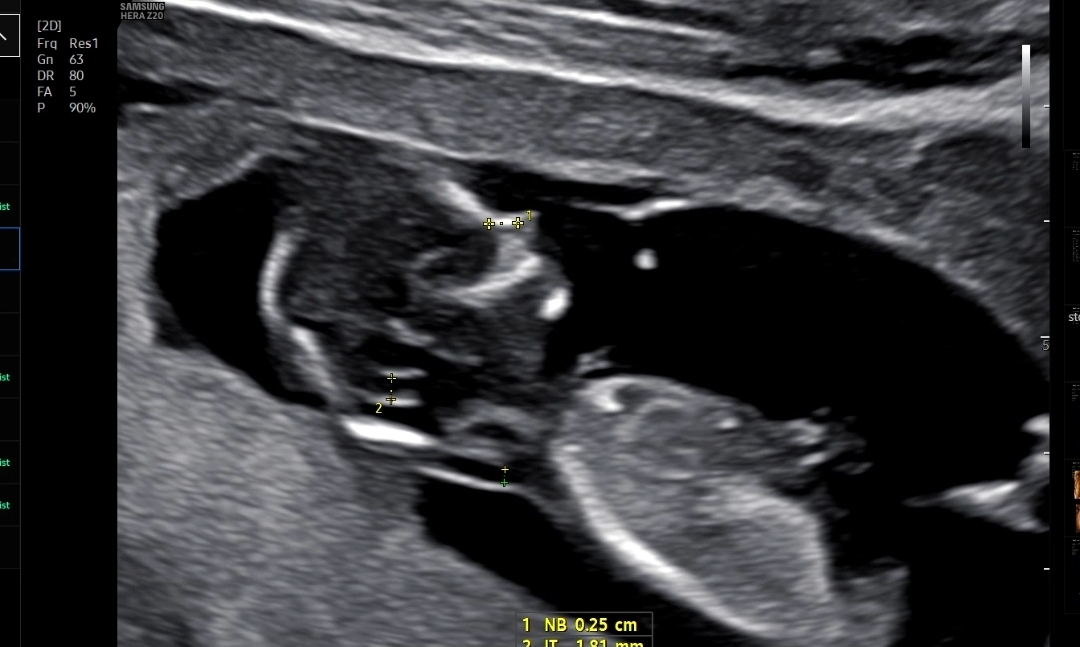

마지막으로 확인한 콧대길이, 소뇌?길이, 목투명대 길이를 쟀다

처음에 계속 뒤돌아 있어서 기침하고 했는데 약 10분간 애쓰다가 겨우 보여준 콧대

코뼈길이는 0.26cm, 목투명대는 1.31mm 로 둘다 정상범위!

만약에 코뼈가 낮거나 목투명대가 3mm이상이면 다운증후군 위험이 있다고 했다